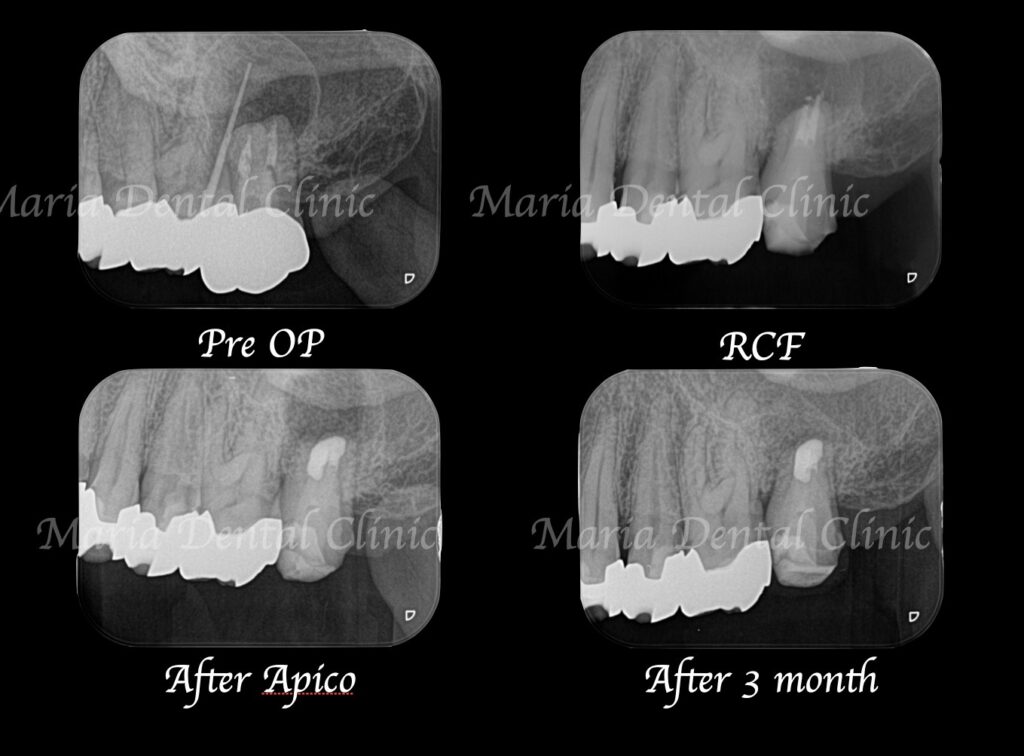

当院で精密根管治療を施しましたが、瘻孔(フィステル・サイナストラクト)を消失させることが難しく、追加処置として歯根端切除術(今回は意図的再植術)を行いました。また、術前に撮影したCT画像より、根尖性歯周炎が原因と考えられる上顎洞炎(蓄膿症/ちくのうしょう)の併発も確認できました。

歯根端切除術(意図的再植術)から3週間後の経過観察で、瘻孔の消失が確認できました。また、術後3ヶ月経つと、根尖部付近に確認できていた根尖性歯周炎も小さくなりました。患者様も「噛んだときにも、違和感や痛みなどはない」ということで、予後は良好だと判断しました。今後は最終補綴処置を行う予定です。

今回の症例の患者様は、病変が大きいことから、かかりつけ医に抜歯を宣告されて、当院へ相談に来られました。当院の治療により、瘻孔(フィステル)は消失し、歯根端切除術(意図的再植術)3ヶ月後の経過観察では、明らかな病変の縮小が確認されました。